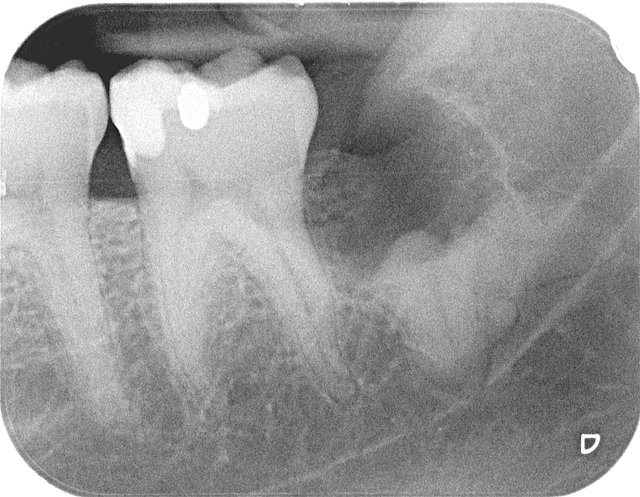

Gekrümmte Wurzeln beim Nervenkanal

Komplikationslose Entfernung ✓

Gekrümmte Wurzelspitzen ... ✓

Wurzelreste beim Nevenkanal

Wurzelreste beim Nervenkanal